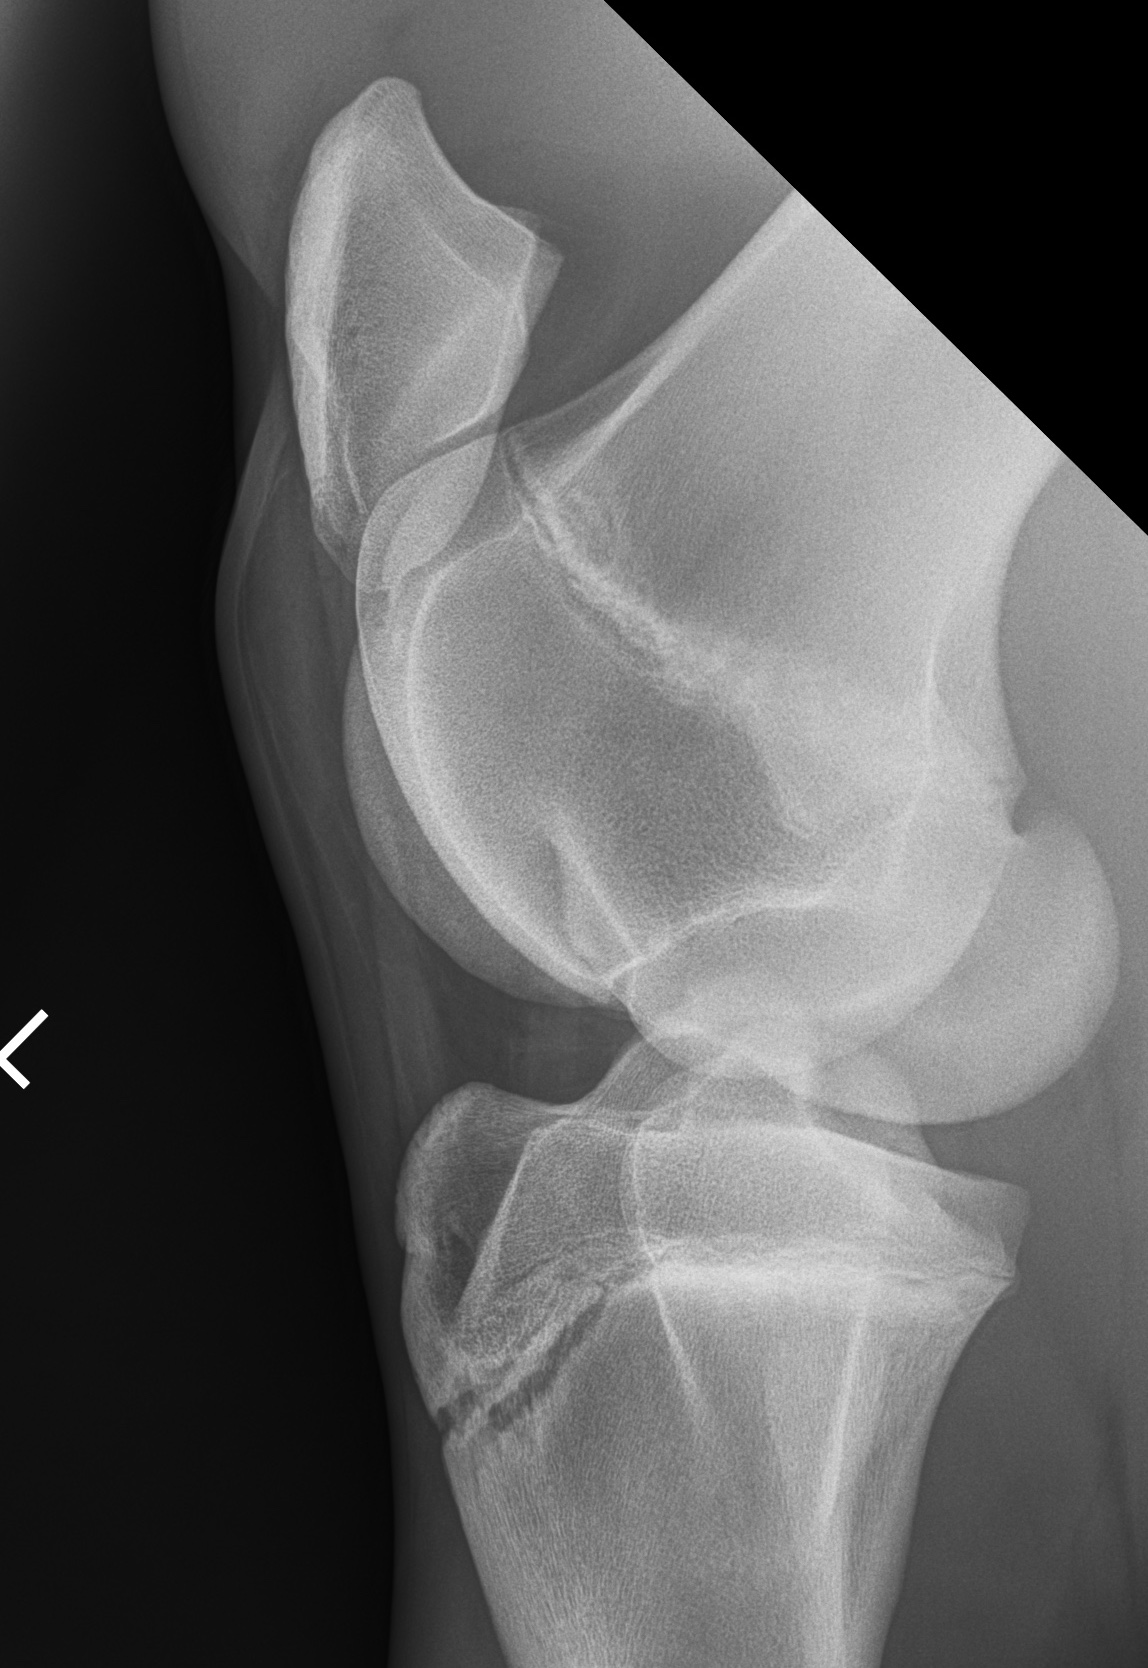

Equine Stifle X Ray The lateral trochlear ridge has lost its regular, rounded appearance and shows an indentation with underlying subchondral bone sclerosis, indicating oc. in severe cases, the horse may carry the leg in a bent position. the stifle joint is an important source of lameness in all types of horses. With good collimation, the lateromedial view does not require the use of a grid. If the cartilage or ligaments of the joint have ruptured, a. the stifle is a complex joint and, when faced with a patient suffering from pain in this area, a veterinary surgeon will often use radiography. by far and away the equine stifle is most commonly radiographed using portable equipment for radiography. stifle radiography in the young performance horse is a fairly routine procedure for most equine practitioners. The proximal margins of the lateral tibial condyle and tibial plateau should be separated by 1 to 1.5 centimeters, not superimposed. the ‘take home’ message here is that the equine stifle is prone to problems that can cause significant lameness, and that need. the radiographic appearance of the stifle of young horse changes during the first 18 months of life but is not well described in. Department of veterinary clinical sciences, university of melbourne, werribee, victoria 3030,. Radiology of the stifle joint of the horse. fragments of bone that have pulled away from the attachment sites of the menisci and stifle ligaments can be seen. (a) lateromedial radiographs of an equine stifle: the precise radiographic anatomy of the soft tissue structures of the equine stifle has not been described.

Equine Stifle X Ray . the ‘take home’ message here is that the equine stifle is prone to problems that can cause significant lameness, and that need. in severe cases, the horse may carry the leg in a bent position. Radiology of the stifle joint of the horse. the stifle is a complex joint and, when faced with a patient suffering from pain in this area, a veterinary surgeon will often use radiography. (a) lateromedial radiographs of an equine stifle: They are used to evaluate for developmental and acquired. the precise radiographic anatomy of the soft tissue structures of the equine stifle has not been described. With good collimation, the lateromedial view does not require the use of a grid. the lateromedial view is the basic radiographic view of the stifle and can be obtained on the standing horse with a portable or fixed radiographic unit. the equine stifle is a large, complex region and its ultrasonographic examination requires a thorough. by far and away the equine stifle is most commonly radiographed using portable equipment for radiography. stifle radiography in the young performance horse is a fairly routine procedure for most equine practitioners. The medial tibial condyle should be flat, not curved. stifle injuries are increasingly recognized as a major cause of hind limb lameness in a normal horse. the stifle joint is an important source of lameness in all types of horses.